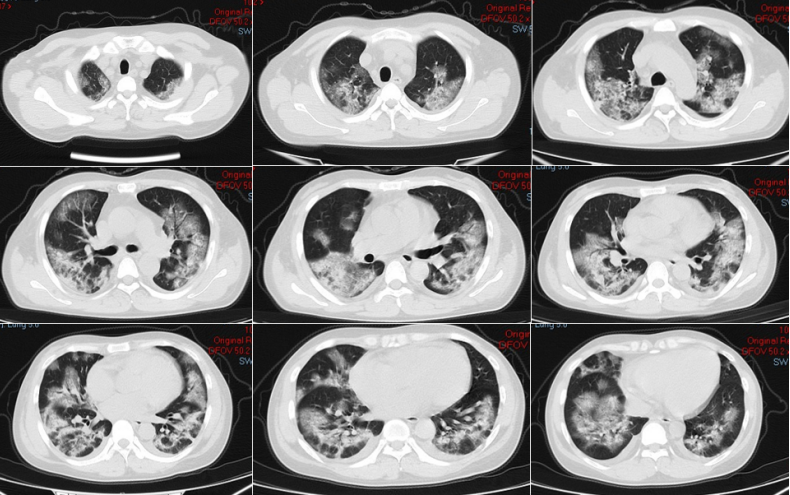

图片

1周后复查胸部CT可见双上肺新发磨玻璃影,双下肺实变为著,影像学较前进展。

2022年12月18日

2022年12月26日

2023年1月6日复查患者胸部CT,已经完全呈“白肺”表现。